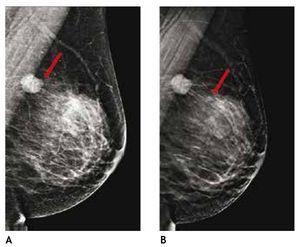

En estas lesiones no palpables, es de gran utilidad la estereotaxia, sistema utilizado ya sea en la mastografía analógica como en la digital, para efectuar la biopsia precisa y exacta, generalmente de microcalcificaciones, mediante pistolas de corte aspiración y vacío, con la paciente sentada o en la mesa prona (figs. 4A y B).

Figura 4 A) Paciente de 51 años, asintomática. Biopsia estereotáxica con sistema corte aspiración, imagen de localización y clip de titanio, rodeado por serohematoma. B) Radiografía de fragmentos con microcalcificaciones (flechas): cáncer ductal in situ con áreas de invasor. C) Marcaje mamario de clip, guiado por radiografía, previo a tratamiento conservador (mismo caso).

También es posible llevar a cabo localizaciones o marcajes mamarios con colocación de un arpón, previo a la biopsia excisional, a través de rejillas fenestradas (fig. 4C).